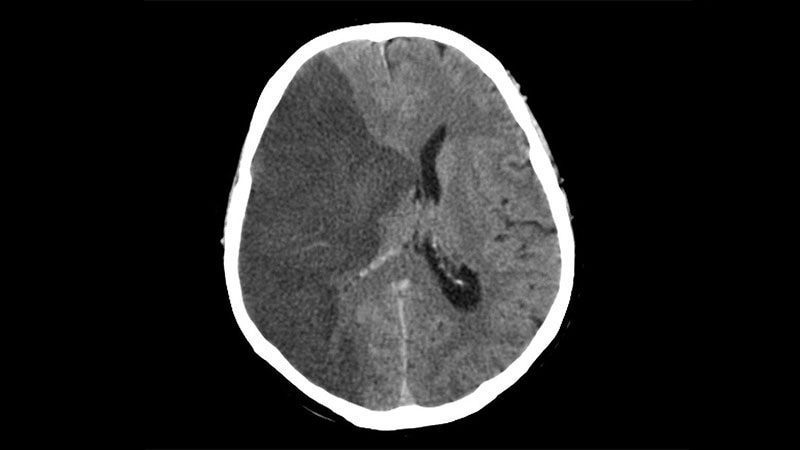

Tenecteplase for Stroke Linked to Reduced ICH RiskA new study shows use of tenecteplase is associated with a lower risk of symptomatic intracranial hemorrhage compared with

the standard alteplase in patients who have suffered stroke.